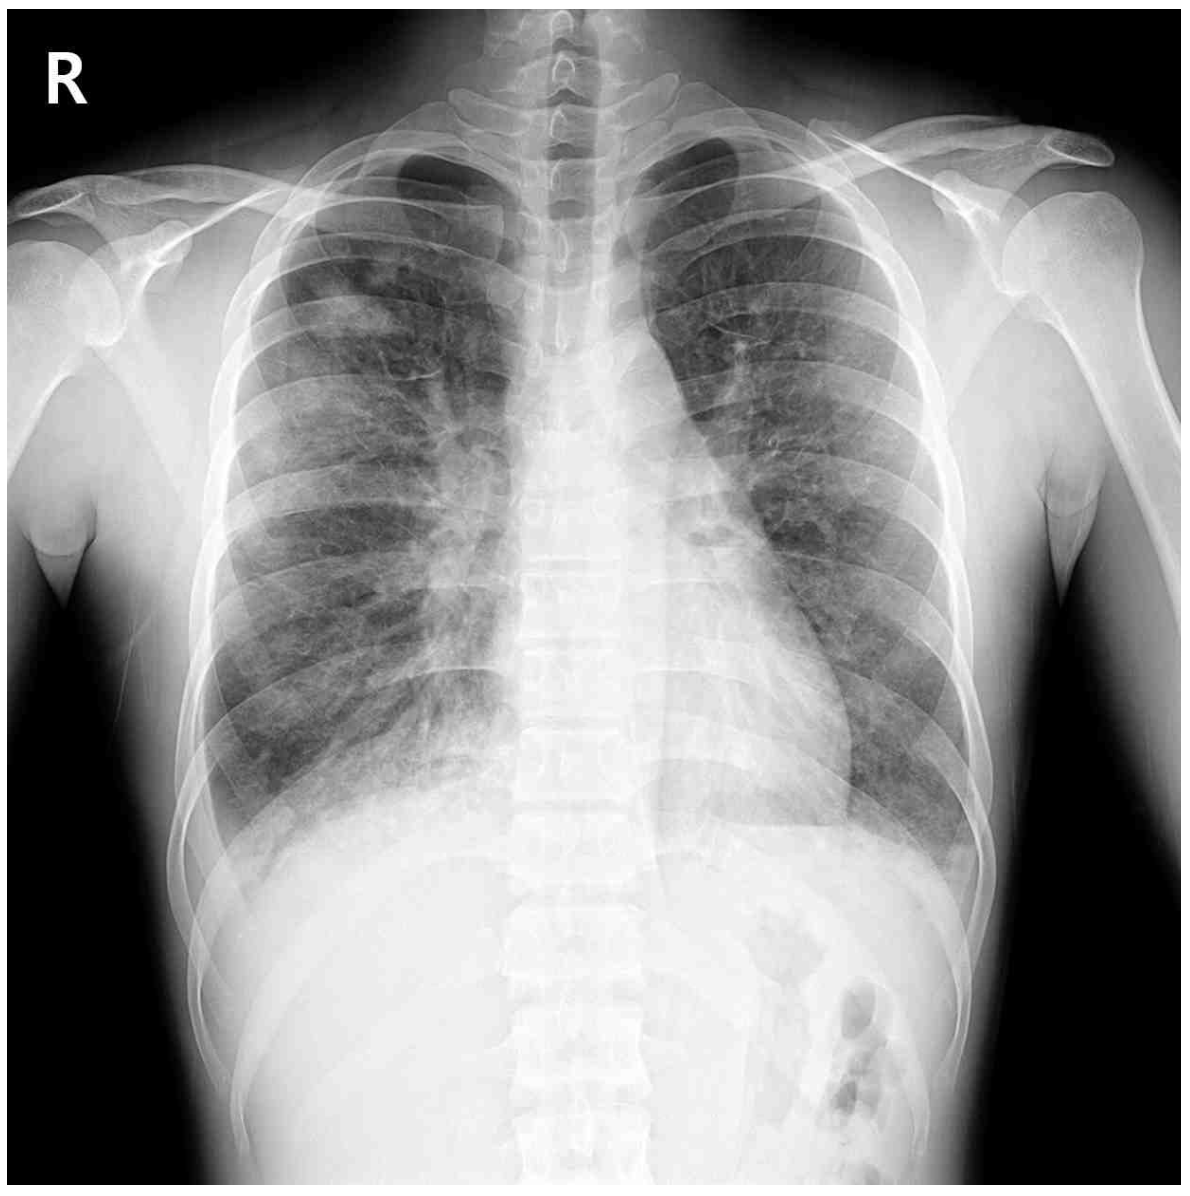

20세 남자가 2일 전부터 기침을 하고 숨이 찬다며 병원에 왔다. 10일 전부터 흡연을 새로 시작하였다. 혈압 124/80 mmHg, 맥박 100회/분, 호흡 22회/분, 체온 37.7℃이다. 양쪽 가슴에서 거품소리가 들린다. 가슴 X선사진, 가슴 컴퓨터단층촬영 사진과 기관지폐포 세척액 파파니콜로 사진이다. 검사 결과는 다음과 같다. 치료는?

CXR, CT: Bilateral multifocal GGO

• CXR 및 chest CT상 multifocal patchy GGO를 양쪽에서 관찰할 수 있으며 혈액검사상 CRP 상승에도 백혈구 수치가 참고치 이내이므로 세균 감염의 가능성은 낮다고 판단할 수 있다. 더불어 말초혈액에서 호산구 수치 역시 5% 이내로 현재 검사 소견만으로는 호산구증가증을 확인할 수 없다.